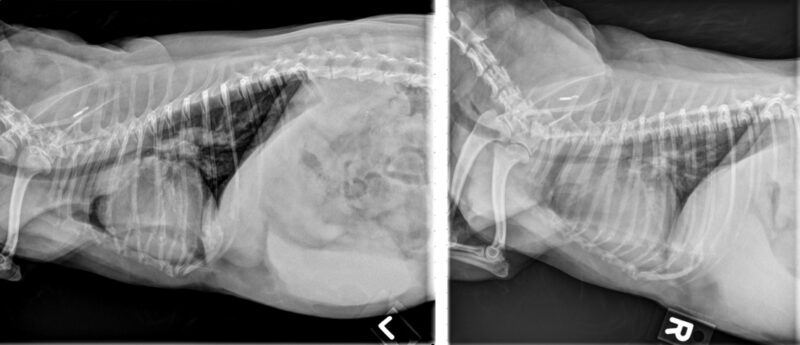

anbei übersenden wir Ihnen die Röntgenaufnahmen unserer Patientin „Valentine“. Es handelt sich um eine 10-jährige, weiblich kastrierte Französische Bulldogge, die in unserer Praxis aufgrund eines seit längerer Zeit bestehenden, chronischen Hustens vorgestellt wurde. Wir würden uns sehr über Ihre Einschätzung der vorliegenden Röntgenbilder freuen: Welche Befunde lassen sich erkennen und welche differenzialdiagnostischen Überlegungen ergeben sich aus Ihrer Sicht?

Dr. Anna Adrian, MS, DACVR, antwortet: Vielen Dank für die Zusendung dieses interessanten Falles. Es liegen eine links- und rechtslaterale sowie eine ventrodorsale Thoraxaufnahme vor. In allen drei Projektionen zeigt sich eine ausgeprägte rechtsseitige Kardiomegalie, die mit einer dorsalen Verlagerung der Trachea sowie einem vermehrten Kontakt des Herzens zum Sternum einhergeht (Bild 1, dunkelblaue Pfeilköpfe). In der ventrodorsalen Projektion imponiert die Rechtsherzvergrößerung als typische „reverse D-Form“ (Bild 2, dunkelblaue Pfeile). Zusätzlich fällt in dieser Ansicht auf Höhe der 2-Uhr-Position eine Vorwölbung auf, die einer Dilatation des Truncus pulmonalis entspricht (Bild 2, dunkelblauer Kreis).

Die kaudalen lobären Pulmonalarterien sind hochgradig erweitert, überschreiten deutlich die Breite der 9. Rippe und zeigen einen geschlängelten Verlauf (Bild 1 und 2, hellblaue Pfeile). Zur Erinnerung Venen liegen in der VD-Aufnahme zentral und in der lateralen Aufnahme ventral, wohingegen Arterien lateral und dorsal gelegen sind. Die Vena cava caudalis erscheint geringgradig dilatiert. Das Lungenparenchym weist insgesamt ein leicht- bis mittelgradig ausgeprägtes bronchointerstitielles Muster auf. Im kranialen Abdomen ist eine kraniale abdominale Organomegalie erkennbar, sowie geringgradige Heterogenität des abdominalen Fettgewebes (Bild 1, hellblau gestricheltes Rechteck). Dieser Befund ist vereinbar mit einer Splenomegalie +/- Hepatomegalie und geringgradiger Aszites. Die übrigen abdominalen Strukturen erscheinen unauffällig.

Zusammenfassend liegen eine ausgeprägte rechtsseitige Kardiomegalie sowie eine deutliche Erweiterung der Pulmonalarterien vor. Die Befundkonstellation spricht für eine pulmonale Hypertension in Kombination mit einer Kardiomyopathie, möglicherweise sekundär infolge einer Herzwurmerkrankung oder eines idiopathischen Cor pulmonale. Zur weiterführenden Abklärung wird eine echokardiographische Untersuchung empfohlen. Das bronchointerstitielle Lungenmuster kann altersphysiologisch bedingt sein, differentialdiagnostisch sind jedoch auch eosinophile Infiltrate im Rahmen einer parasitär bedingten Hypersensitivitätsreaktion in Betracht zu ziehen. Die Dilatation der Vena cava caudalis kann einerseits ein Normvariant darstellen, andererseits im Kontext der Rechtsherzvergrößerung auf eine Rechtsherzinsuffizienz oder ein Vena-cava-Syndrom bei hoher parasitärer Last hinweisen.